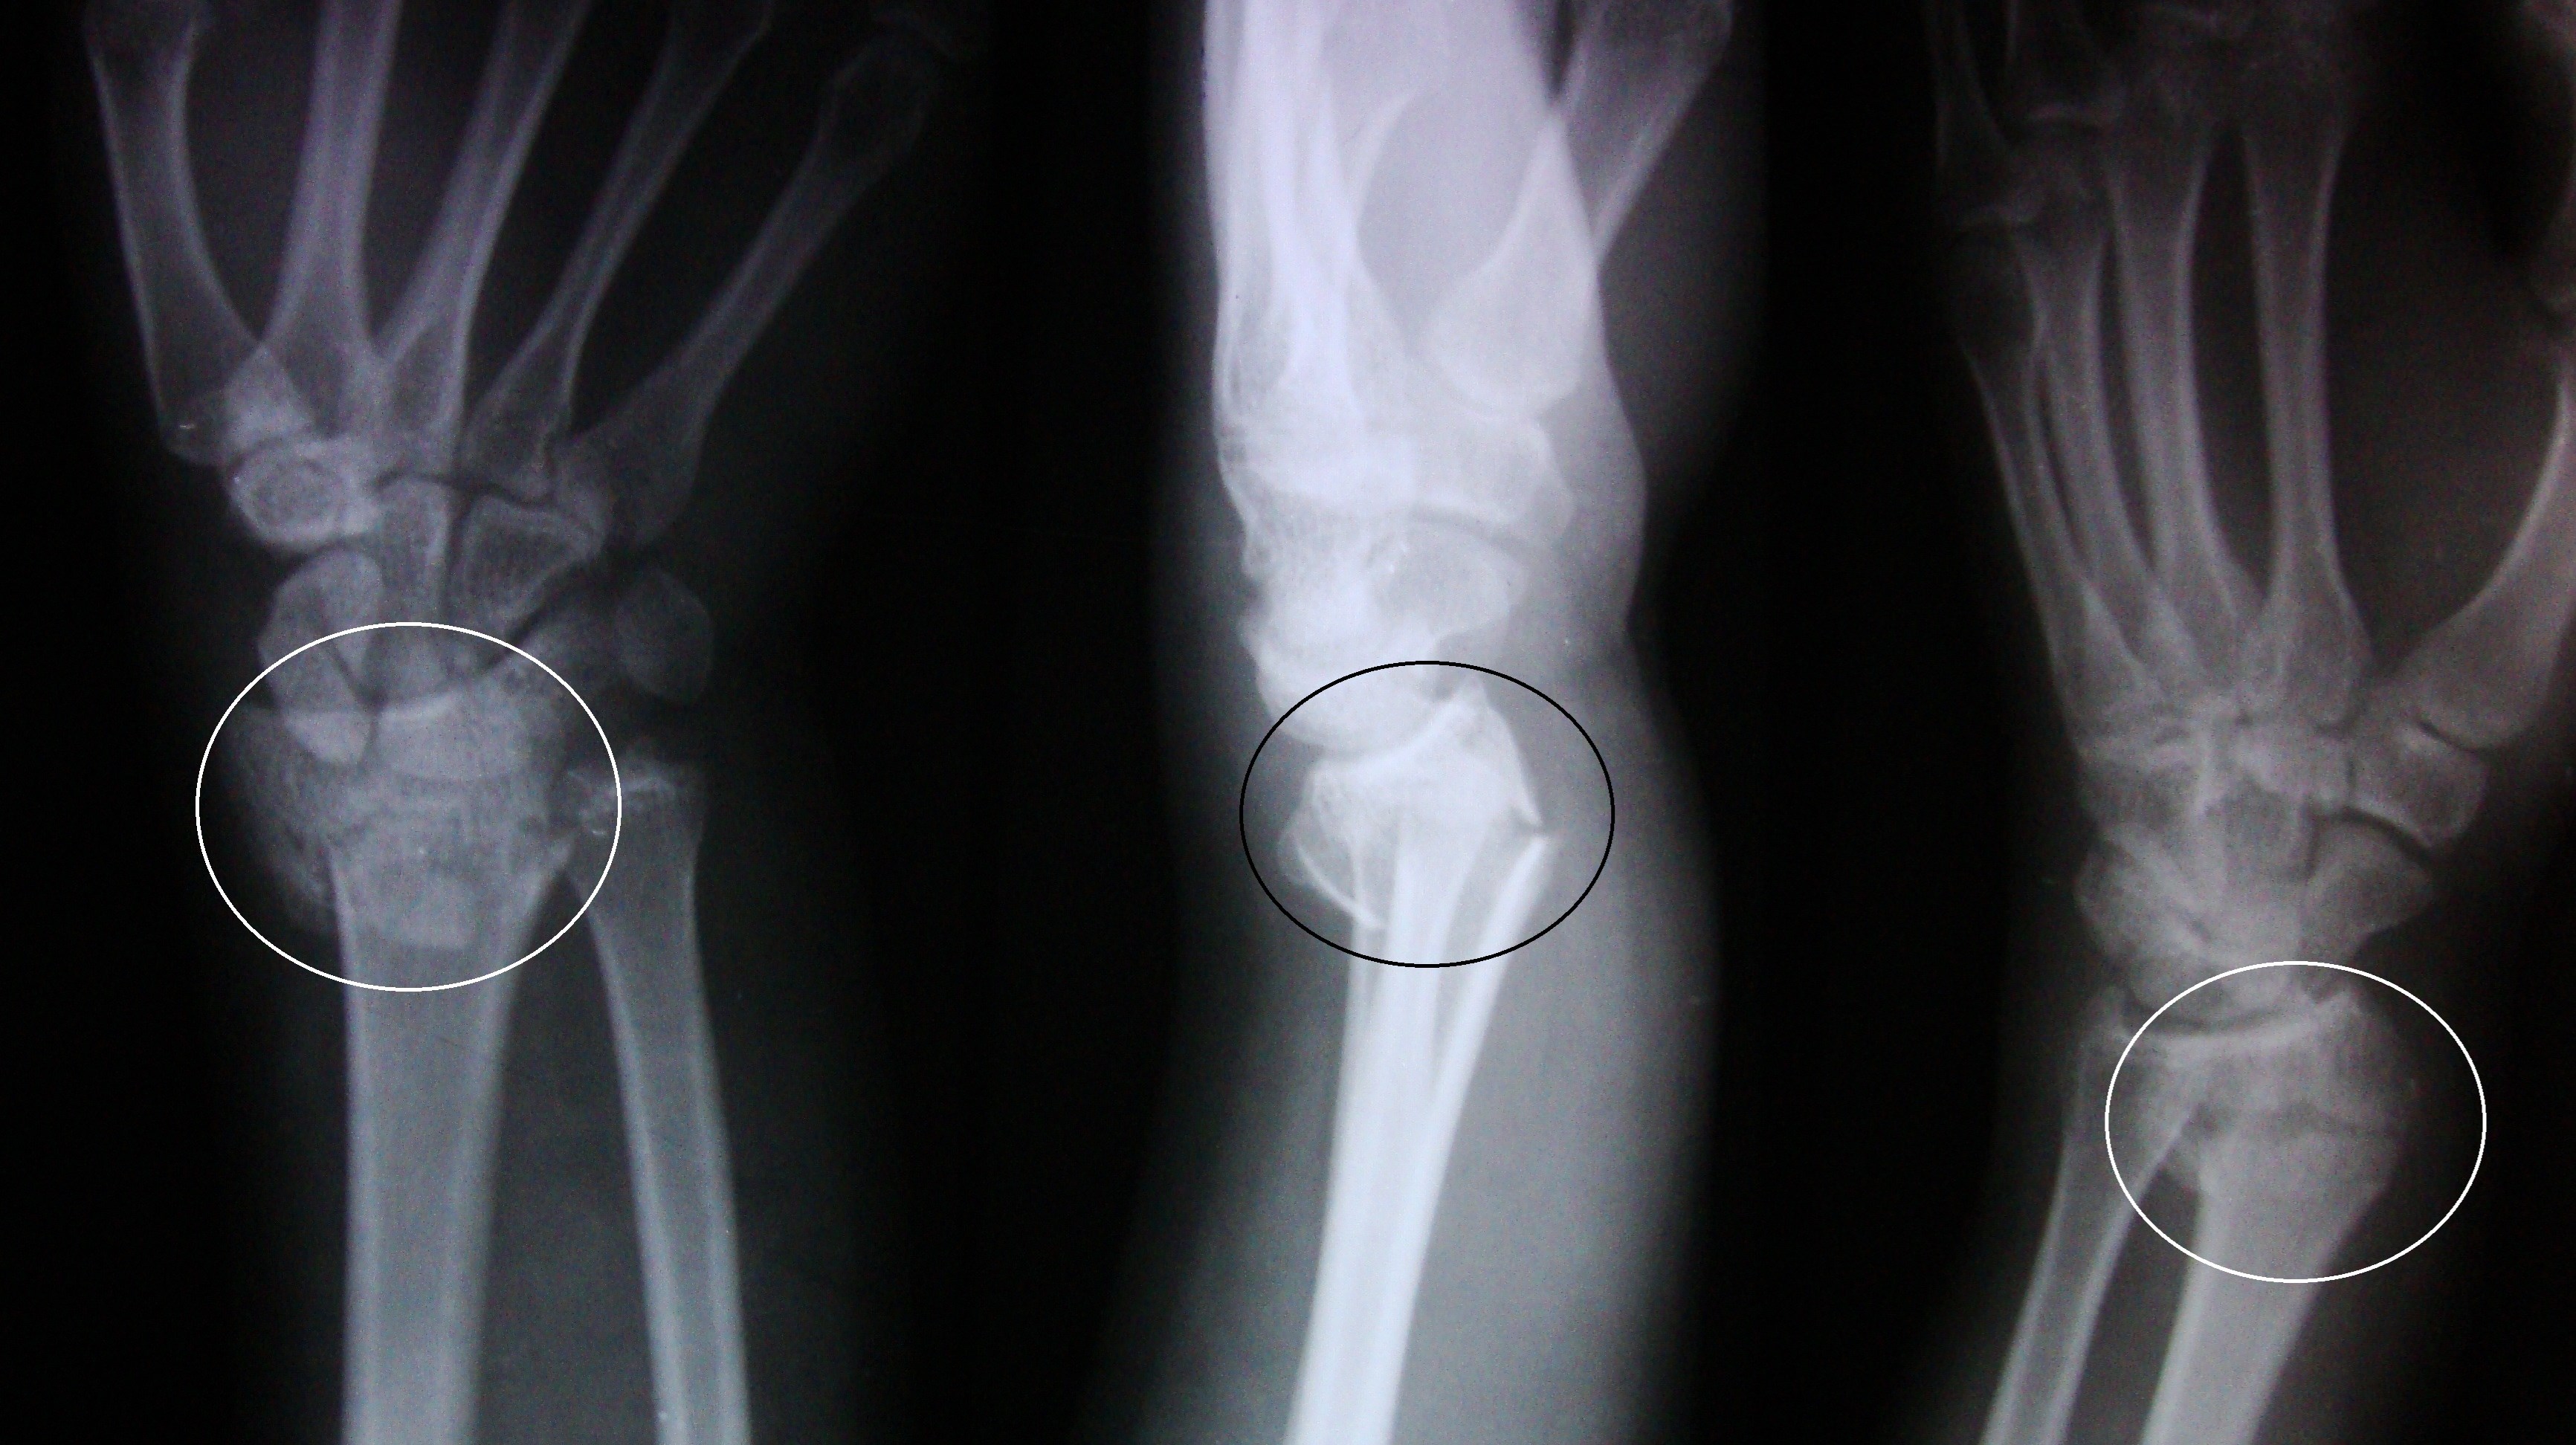

Bennetfraktur

Bennetfraktur är en intraartikulär luxationsfraktur genom basen av metacarpale I. Metacarpalbasen tenderar att luxera genom APL senans dragning i radiell-proxmal riktning. Frakturen behöver därför i princip alltid reponeras och immobiliseras internt med stift. Kan se väldig beskedlig ut på primära bilder men dislocerar succesivt genom senans dragning – klassificeras därför som ”lurig”.

Mekanism vid Bennetfraktur

Bennetfraktur där det ulnara fragmentet i basen på metkarpalen hålls kvar med hjälp av ligament i karpus. På grund av drag i abductor pollicis longus (APL) uppstår nästan alltid en diastas i frakturen. Diastasen i ledytan ger sekundärt artros. Dessa frakturer kräver således exakt fixation – vanligen i form av stift eller skruv.